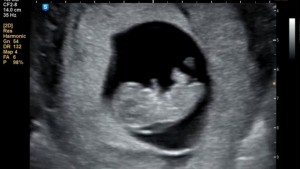

28주 입체초음파 성공!!

닉네임_박*영_43

2025-08-21